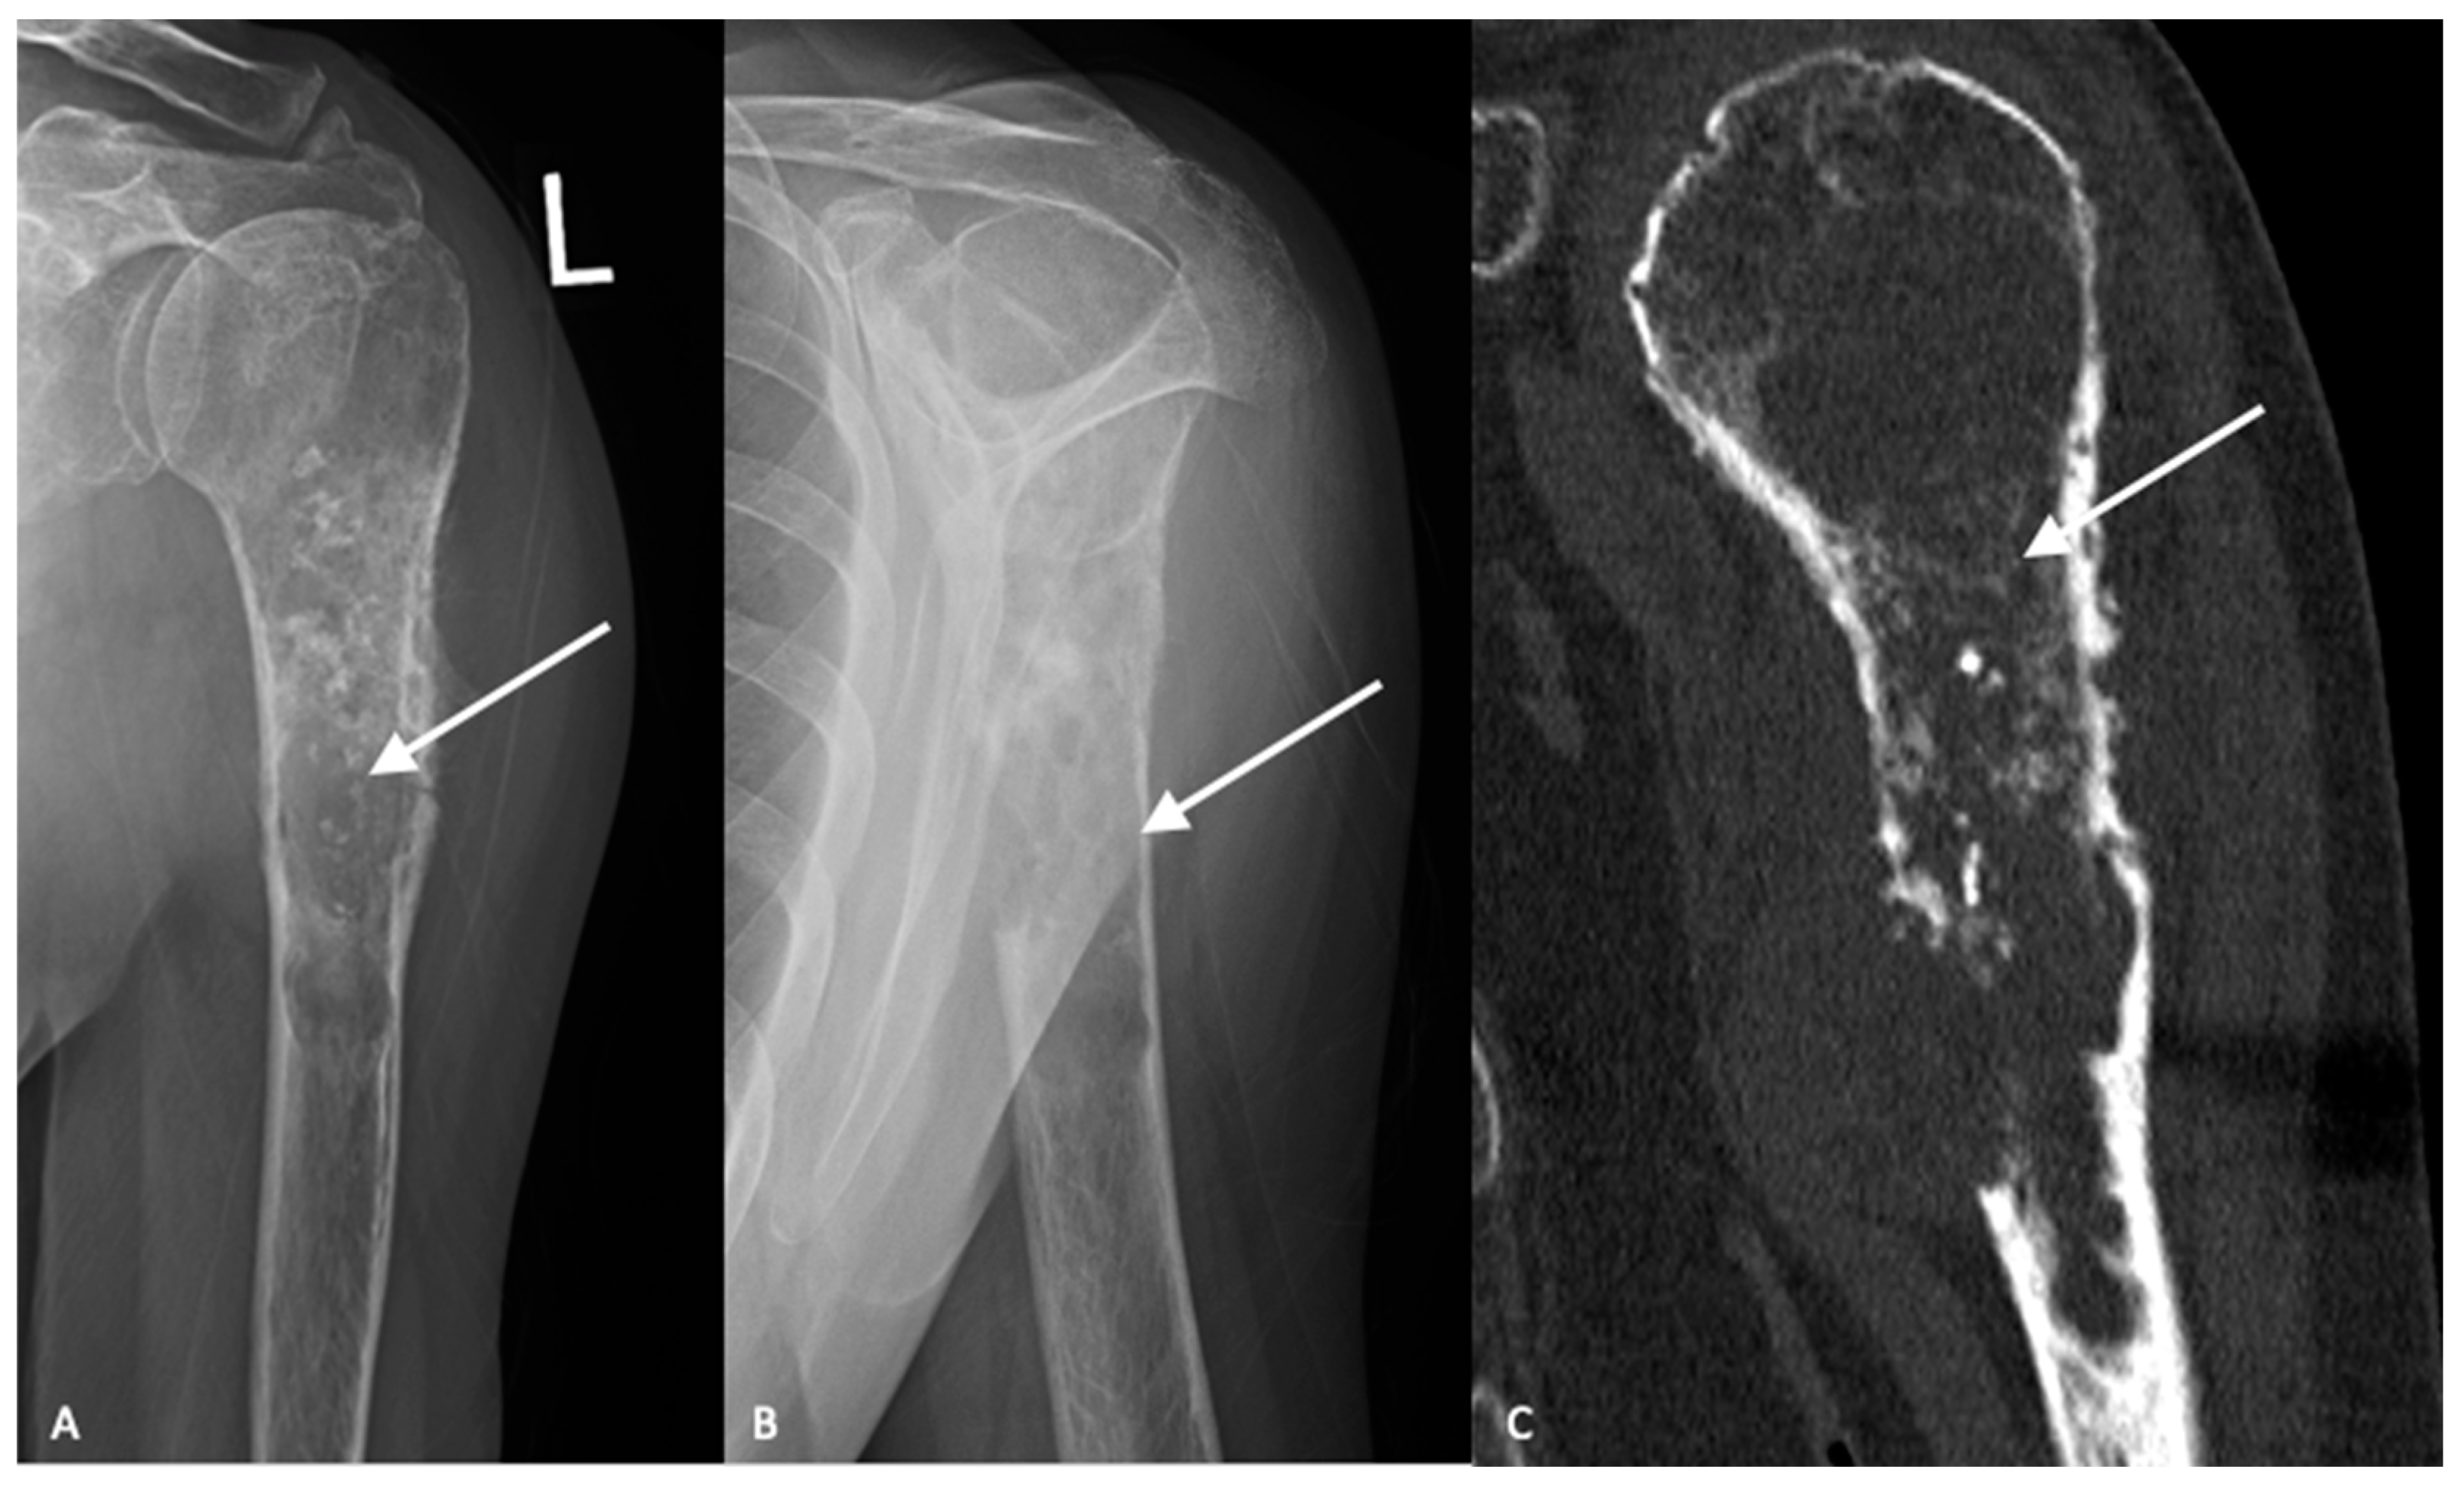

High-grade tumors usually present as larger lesions with less mineralization, with a moth-eaten appearance and permeative bone destruction (Figure 2A,B) [15]. Higher-grade lesions can cause more extensive endosteal scalloping that can result in cortical destruction or pathologic fracture. Soft tissue masses are seen in approximately 50% of cases. However, despite these characteristic differences, plain radiographs are not reliable in determining tumor grade [15].

Magnetic resonance imaging (MRI) with and without contrast is the gold standard in diagnostic imaging for chondrosarcomas [16,17]. Magnetic resonance imaging of the entire bone should be performed to assess for skip lesions. MRI clearly demonstrates the extent of the tumor, invasion into the surrounding soft tissues and relationship to surrounding critical structures. Typically, chondrosarcomas demonstrate low intensity on T1-weighted images, high intensity on T2-weighted imaging with post-contrast enhancement depending on the histologic grade [18]. Computed tomography is the best modality to visualize bony destruction and the pattern of matrix mineralization but is not required for diagnosis (Figure 2C).

Figure 2. AP (A) and lateral (B) radiographs demonstrate an aggressive, heterogenous lytic lesion in the left proximal humerus with a wide zone of transition (white arrows). The lesion measures greater than 5 cm in length. Chondroid matrix is demonstrated. Periosteal reaction is present at the lateral aspect. There is a large area of cortical breakthrough at the anterior cortex, in addition to numerous areas of endosteal scalloping. Computed tomography (C) further demonstrates the cortical disruption and chondroid matrix formation (white arrow).